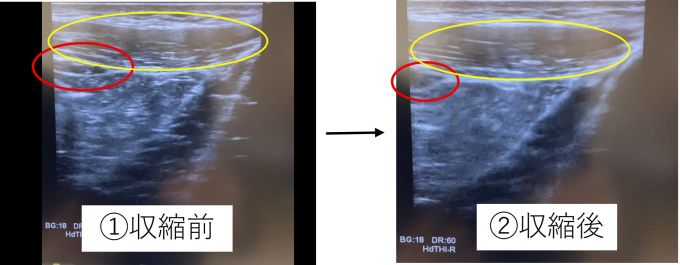

筋肉の収縮にはいくつか種類がありますが、主にトレーニングで用いるのには「求心性収縮」と「遠心性収縮」の二種類です。

スクワットをする時の大腿四頭筋(ふとももの前面の筋肉)を例にすると、膝を伸ばして立ち上がる時の収縮が「求心性収縮」、ゆっくり膝を曲げていく時の収縮が「遠心性収縮」です。

この二つの収縮ですが、「求心性収縮」よりも「遠心性収縮」の方が筋力増強・筋肥大が起こりやすいといわれており、「遠心性収縮」をうまく使うと効率よくトレーニングが行えます。

具体的には力を入れて曲げたり伸ばしたりする「求心性収縮」に2秒、元の位置に戻す「遠心性収縮」に4秒、時間をかけてみましょう。

ゆっくり戻すことを意識するだけで、これまで楽にできていたトレーニングでもきつく感じるようになるかもしれません。

せっかくのトレーニング、効果的かつ効率的にトレーニングを行いましょう。